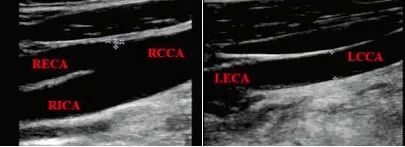

此时进行颈部血管超声检查,发现:双侧CCA管径不对称,RCCA管径9.5 mm,向上分出RECA后,延续为RICA;LCCA管径4.5 mm,向上未见分叉,直接延续为LECA,LICA管腔未显影,如下图,颈部血管超声提示LICA先天未发育。